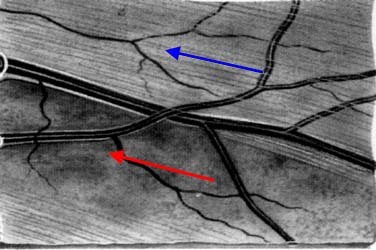

Modrá šipka - ukazuje plochu na sítnici, která obsahuje nervová vlákna. Sítnice je jemně proužkovaná, světlejší, cévy "jsou jako pod závojem". Červená šipka - ukazuje místo bez nervových vláken. Sítnice je tmavší, bez proužkování. Cévy jsou ohraničeny neobvykle ostře.